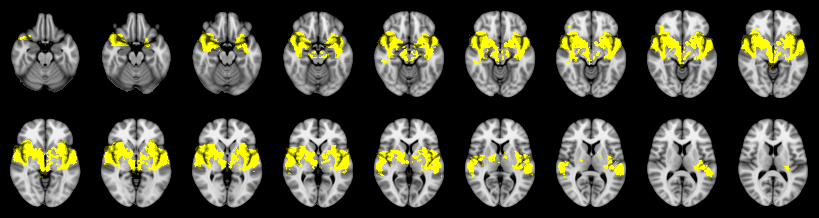

Combined

Friston:

IUT/Conjunction/Nichols:

(cluster statistics not available for IUT)